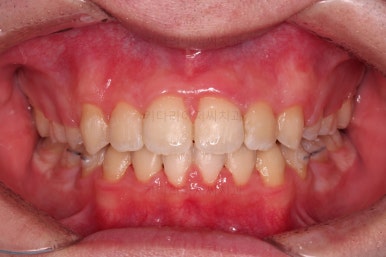

초진 시, 입안의 모습입니다.

치아를 모두 담기에 골격이 매우 작았어요.

이런 경우 치열이 ㅃ뚤어지거나 입이 튀어나오거나 뻐드렁니가 되거나 특정 치아가 묻혀버리거나 맨 뒤치아가 마치 사랑니처럼 올라오지 못한다거나 등등의 문제가 생기는데요.

이번 환자분은 전반적으로 삐뚠 상황이었어요.

앞니도 대칭적으로 삐뚤어져 흔히 나비치아라고 하는 형태로 보이고, 아랫니들은 U자 아치의 형태가 찌그러져 있네요.

당연히 교합도 맞지 않고요.